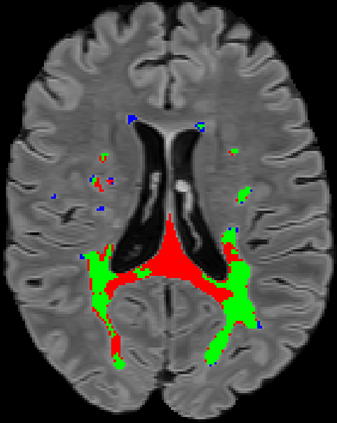

Recently, segmentation methods based on Convolutional Neural Networks (CNNs) showed promising performance in automatic Multiple Sclerosis (MS) lesions segmentation. These techniques have even outperformed human experts in controlled evaluation conditions such as Longitudinal MS Lesion Segmentation Challenge (ISBI Challenge). However state-of-the-art approaches trained to perform well on highly-controlled datasets fail to generalize on clinical data from unseen datasets. Instead of proposing another improvement of the segmentation accuracy, we propose a novel method robust to domain shift and performing well on unseen datasets, called DeepLesionBrain (DLB). This generalization property results from three main contributions. First, DLB is based on a large group of compact 3D CNNs. This spatially distributed strategy ensures a robust prediction despite the risk of generalization failure of some individual networks. Second, DLB includes a new image quality data augmentation to reduce dependency to training data specificity (e.g., acquisition protocol). Finally, to learn a more generalizable representation of MS lesions, we propose a hierarchical specialization learning (HSL). HSL is performed by pre-training a generic network over the whole brain, before using its weights as initialization to locally specialized networks. By this end, DLB learns both generic features extracted at global image level and specific features extracted at local image level. DLB generalization was validated in cross-dataset experiments on MSSEG'16, ISBI challenge, and in-house datasets. During experiments, DLB showed higher segmentation accuracy, better segmentation consistency and greater generalization performance compared to state-of-the-art methods. Therefore, DLB offers a robust framework well-suited for clinical practice.